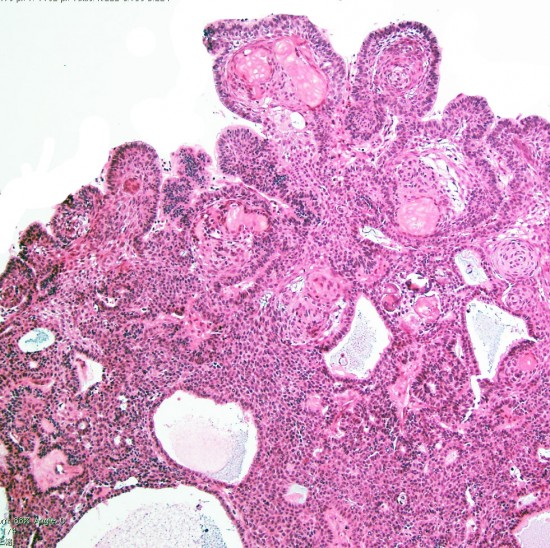

Adamantinomatous craniopharyngioma showing well-differenciated squamous epithelium including whorl of squamous cells. MIB-1 index of the dense basal layer was approximately 10%.